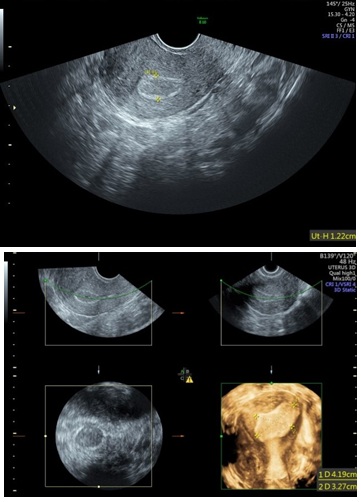

Figure 2: 2D & 3D USG showing Unicornuate Uterus.

Hysteroscopy showing Unicornuate Uterus.

Three-Dimensional Ultrasonography (3D USG) in comparison to hysteroscopy is less invasive, cheaper, easily accepted by most patients and does not require much training. In most cases an endometrial polyp can be differentiated from the submucous fibroid based on the imaging characteristics. The polyps are typically round in shape, smooth in outline, and are generally echogenic, compared to the endometrium or are isoechoic to it. The underlying endometrial-myometrial interface is preserved (Figure 5). Moreover the presence of a vascular pedicle has a positive predictive value of up to 81.3%. Fibroids are more inhomogeneous, hypoechoic, and there is a loss of endometrial-myometrial interface. The percentage of the intra cavitary portions of the submucous fibroids i.e., grade of submucous myoma can be assessed on 3D USG by the degree of distortion caused by it (Picture 6).